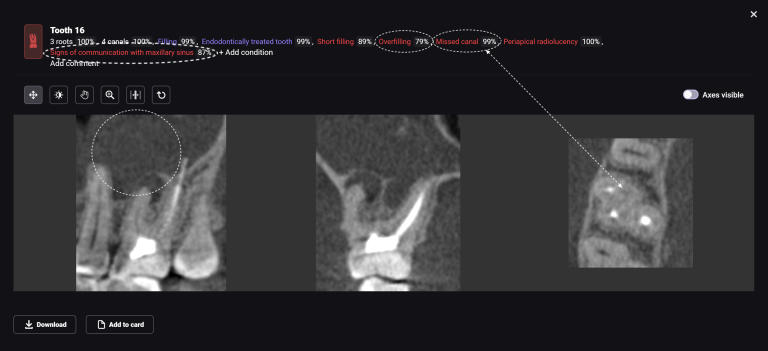

Diagnocat radiological report features an “Conditions with low probability” function. In this mode, teeth marked as “Low probability” are highlighted in yellow. Conditions such as caries and periapical lesions with a probability ranging from 30% to 50%

If the probability percentage is over 50%, the teeth are highlighted in red, and the report contains information about the localization and depth of the lesions